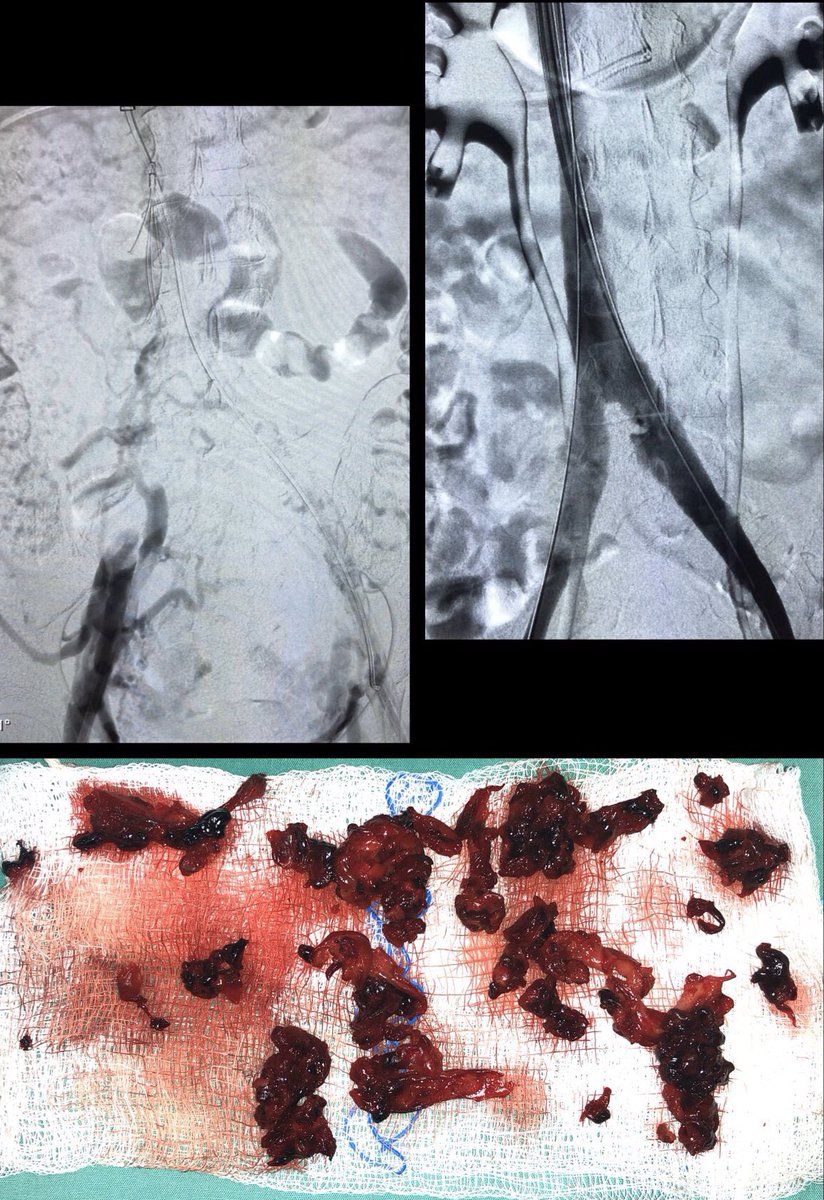

3 month old #IVCfilter with iliocaval occlusion, bilateral leg edema. Crossed both CIV occlusion from below, forceps #Filterout with 18Fr sheath then 18mm wallstent iliocaval reconstruction. #WeCanRecan